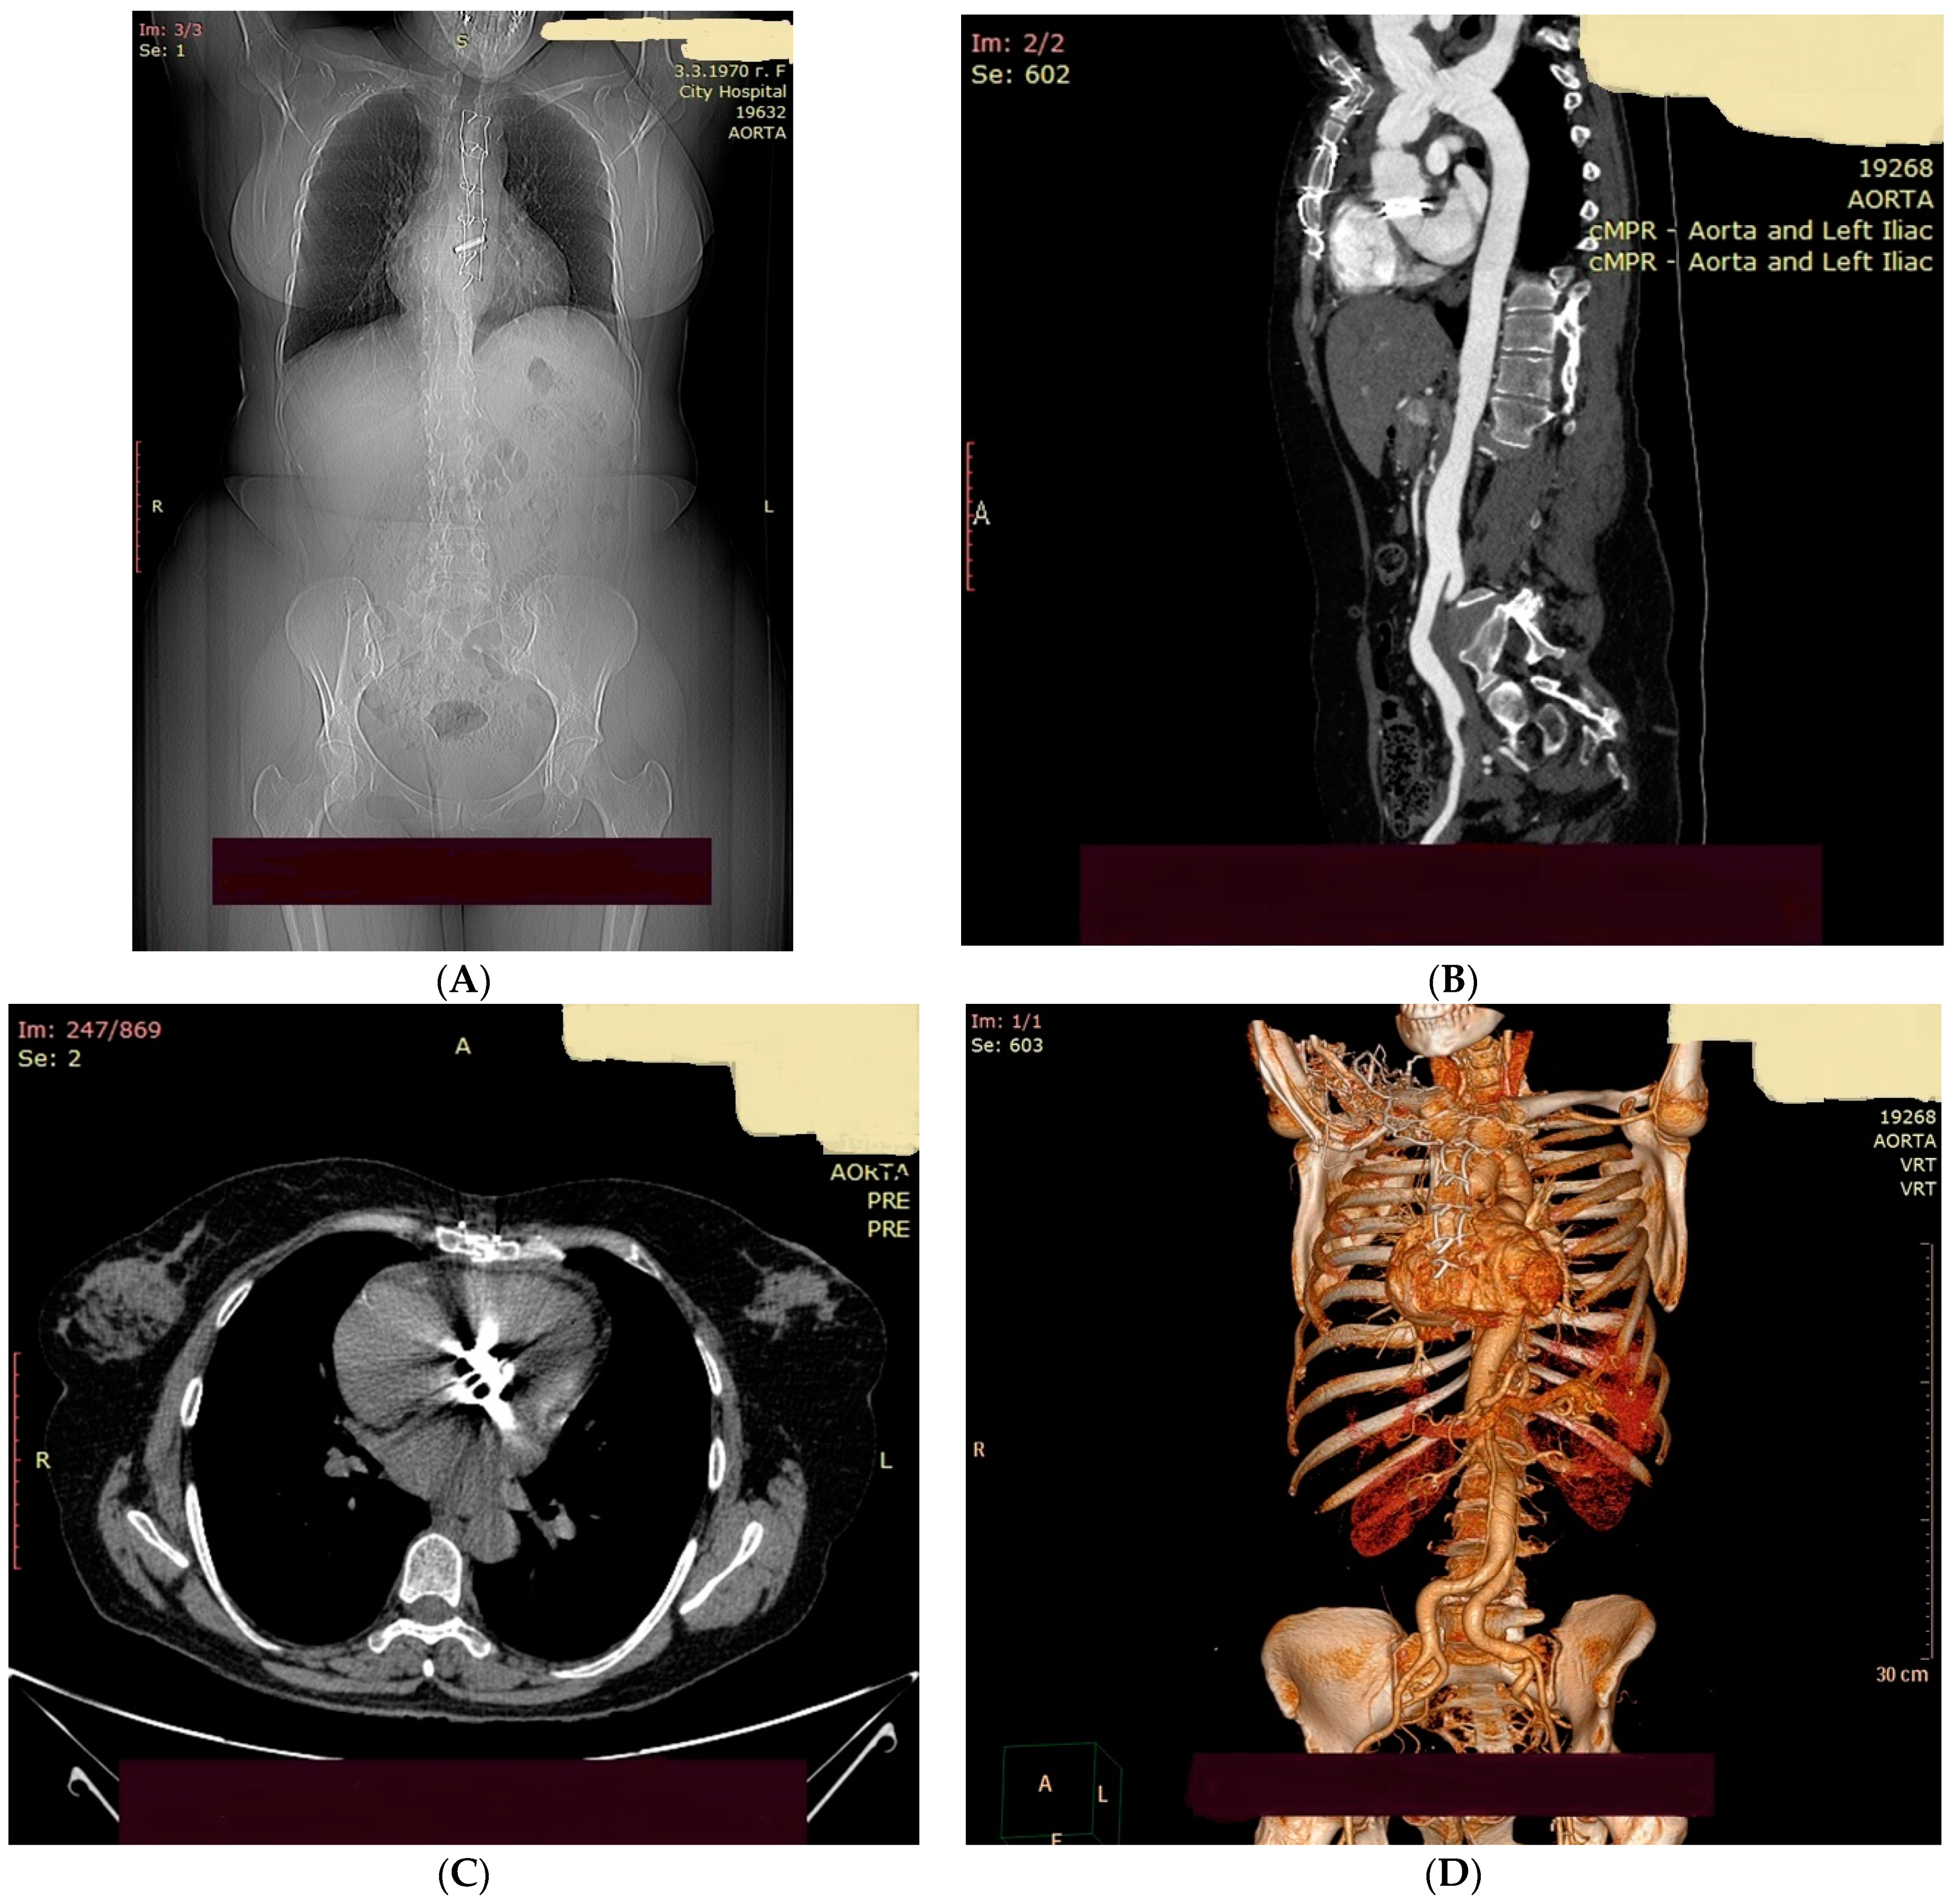

2. Case Presentation